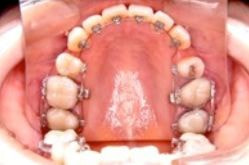

メリット

* 歯の裏側に付ける為、装置が見えない

デメリット

* サ行・タ行の発音が治療当初不明瞭

(2~3ヶ月で慣れてきます)

* 歯みがきが難しい

* 治療当初、舌への違和感がある

* 1回の治療時間が表に比べて長い

大人の方で、仕事の都合でどうしても表側につけられない患者さん向けの方法です。